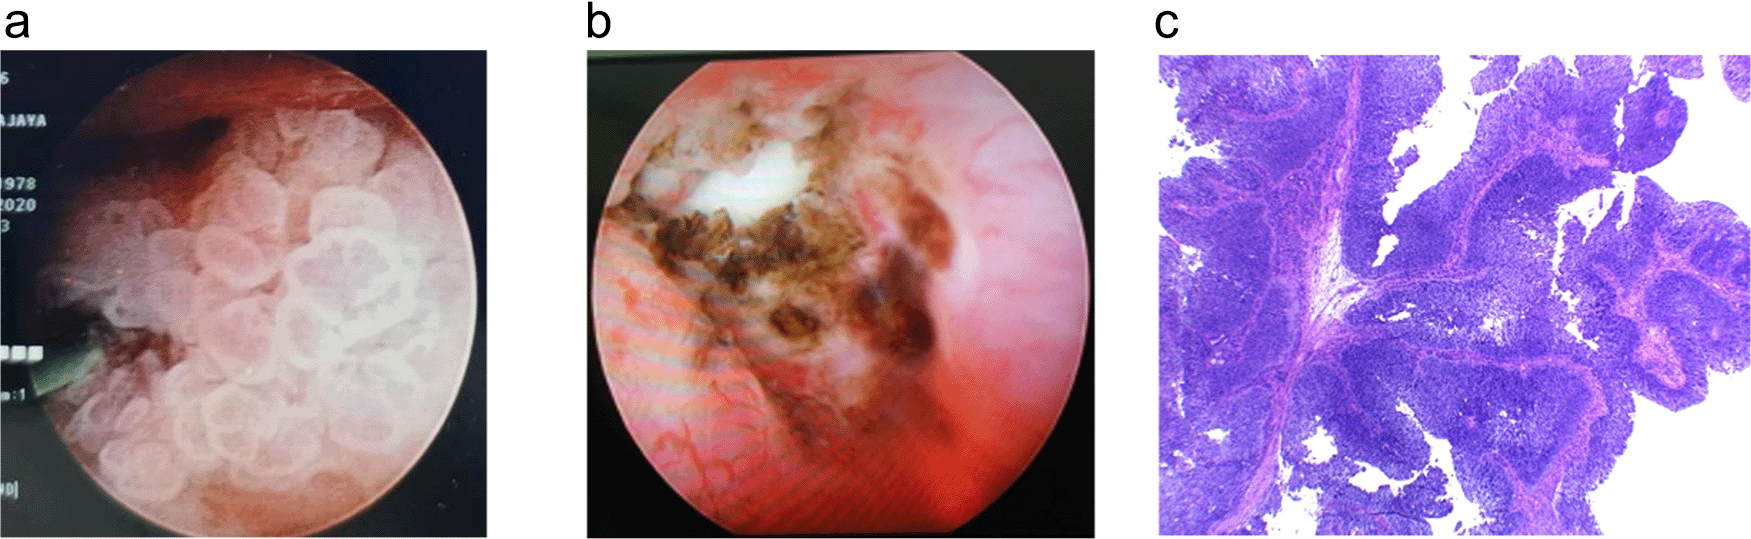

In November 2018, a left open radical nephroureterectomy was conducted to remove the mass, followed by six cycles of adjuvant chemotherapy of gemcitabine-cisplatin. Furthermore, a routine ultrasound and MRI were followed up every three months, and the indwelling catheter was replaced every two weeks. During the follow-up, the patient worked as a chef in satay shop and had a “tumor-free” period of 26 months with a Karnofsky score of 90. This continued until the patient was re-admitted with fever and an increase in creatinine value of 4.3 in August 2020. Then MRI was performed, and hyperintense solid mass was seen in the right renal pyelum. This mass measured 2.2 × 2.1 cm with left hydronephrosis grade II-III and surgery was planned for August 2020. In addition, a puncture was made in the right flank to the superior calyx guided by fluoroscopy into the pelvicalyceal system during the surgery. A nephroscope was then inserted, which exposed a tumor on the right pyelum sized about 3 cm (Figure 4a). The tumor was then extracted using forceps for biopsy, and the residue was evaporated using a laser. Furthermore, nephroscope post-laser ablation examination shows some tumor residue (Figure 4b). The biopsy result was a urothelial carcinoma infiltrative high grade.

(a) Nephroscopy examination in pelviocalyceal system inserted through the right flank reveals a tumor sized about 3 cm. (b) Ureter post evaporation using laser shows some tumor residue even after laser procedure. (c) Tissue fragments containing papillary, infiltrative epithelial malignant tumors with fibrovascular stalk Hematoxylin and Eosin stain (H&E) stain 40×.